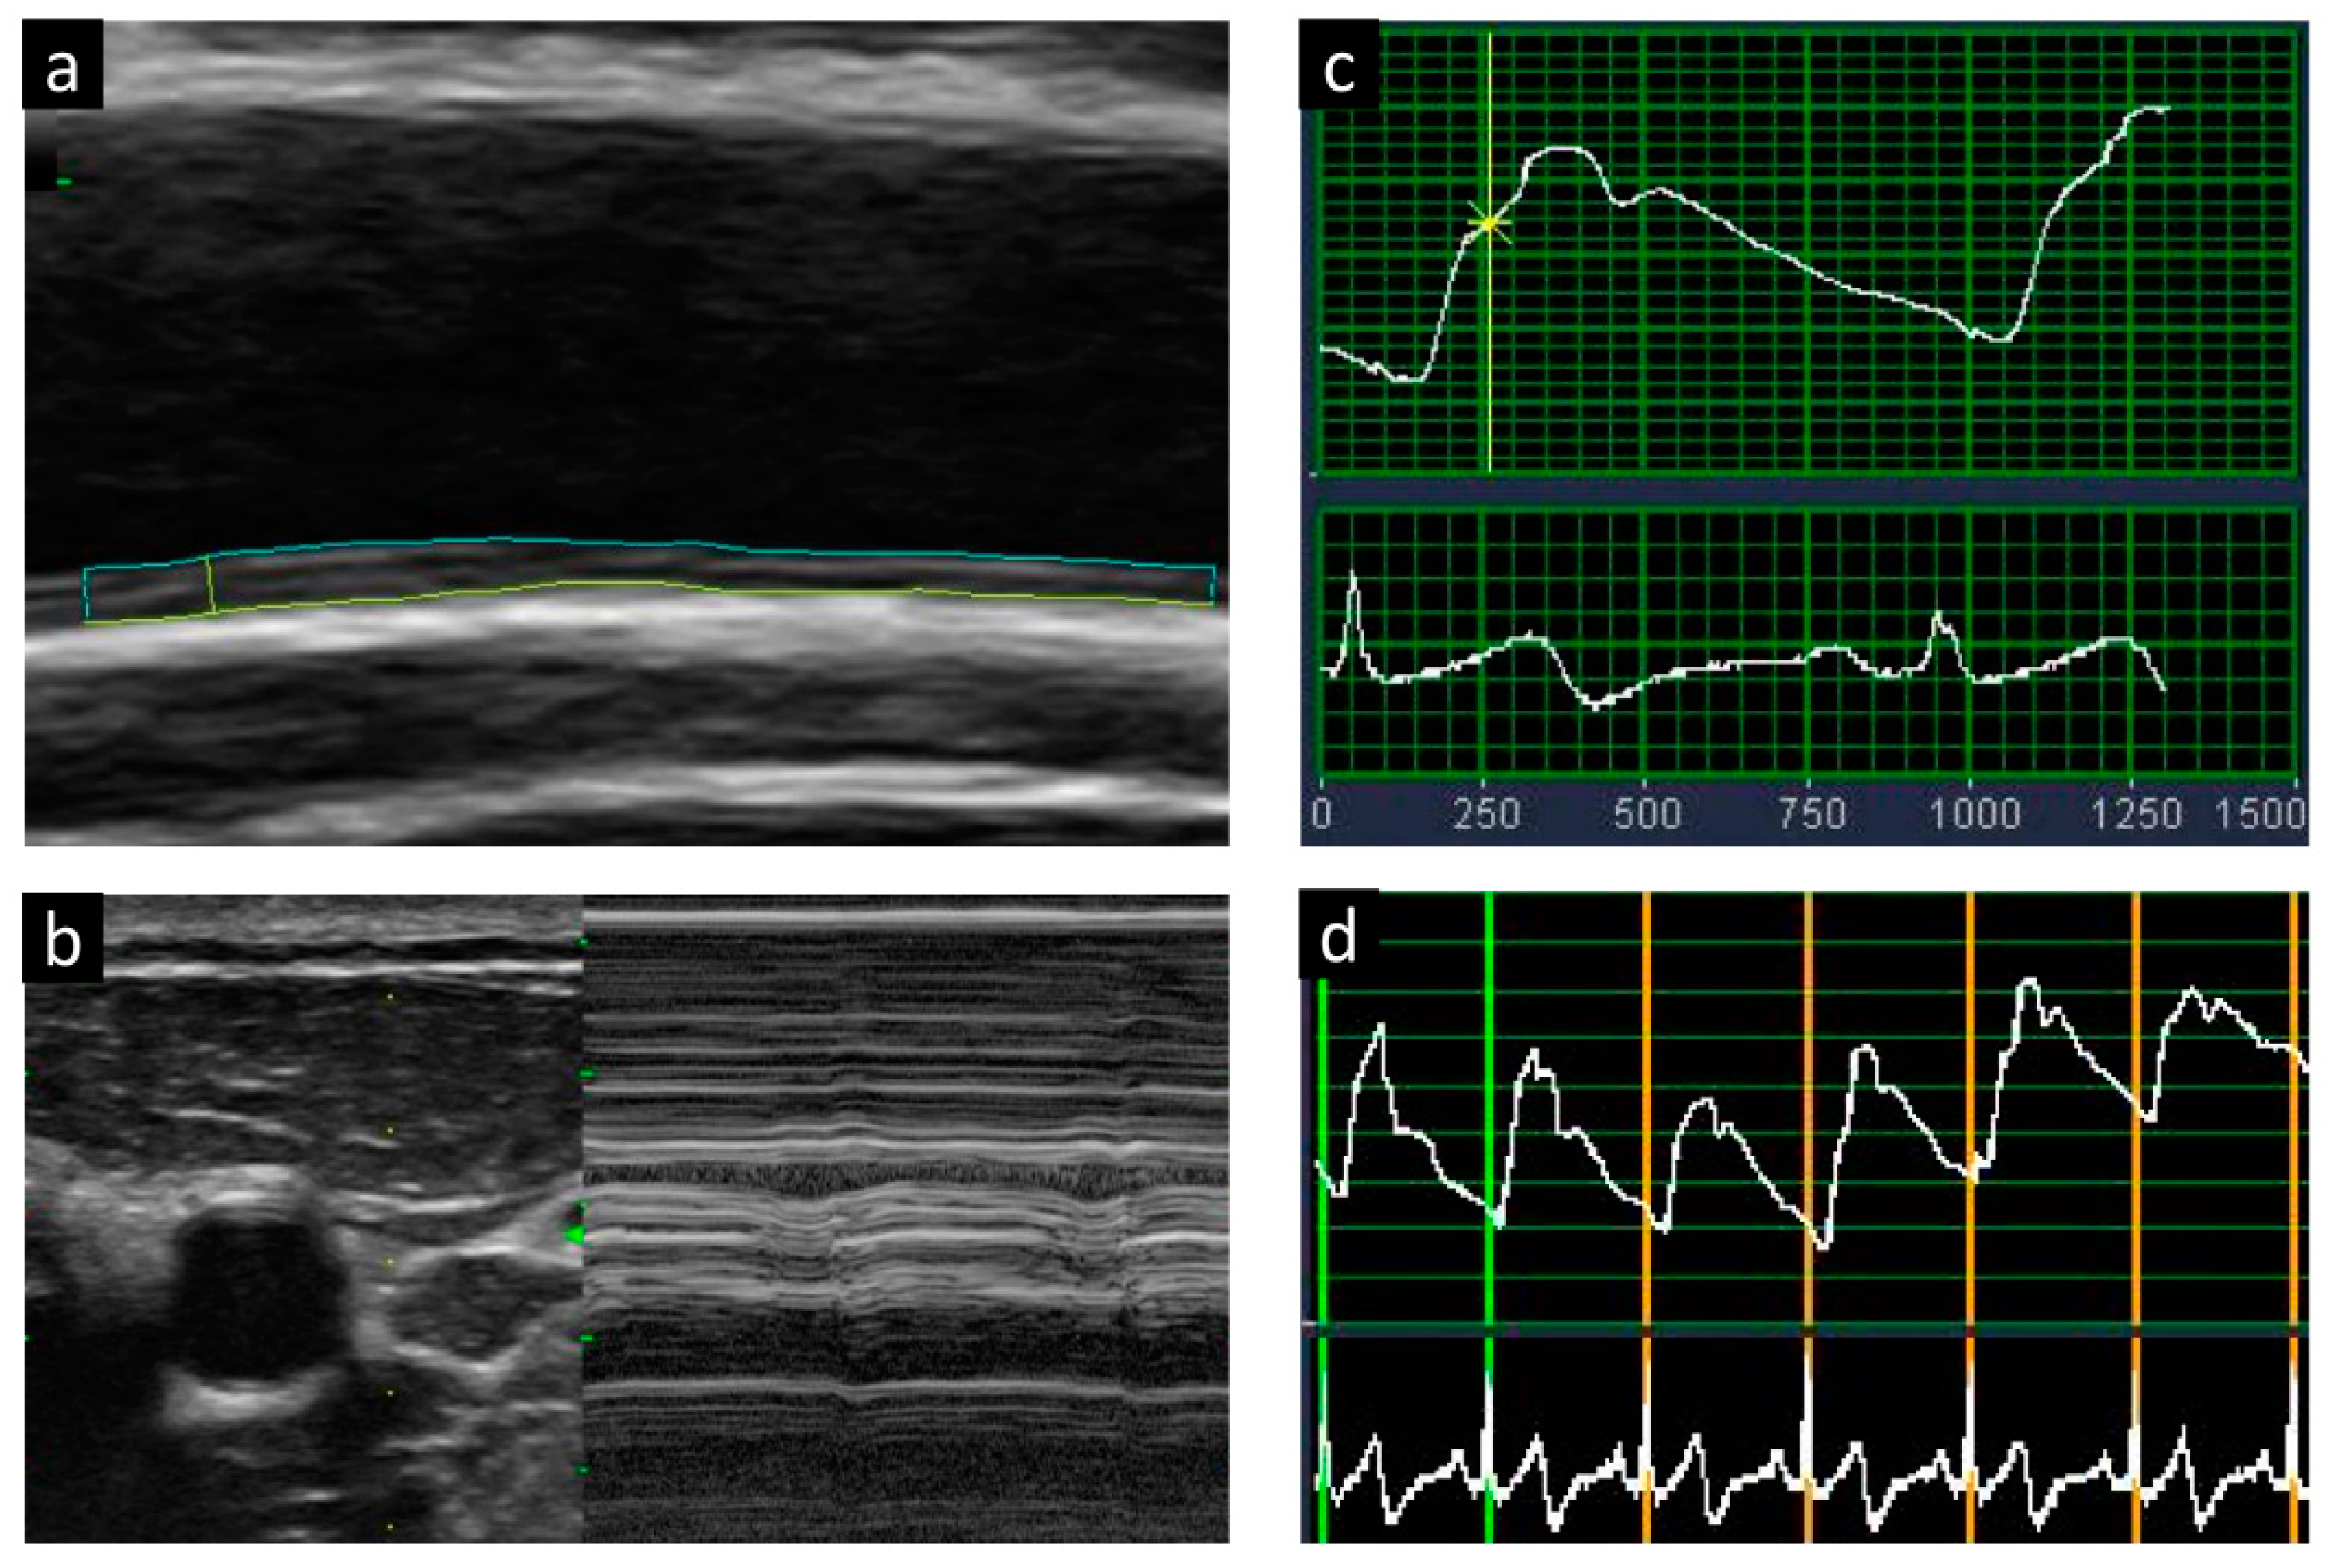

2.3. Ultrasound Examination for Carotid Plaque and Arterial Stiffness